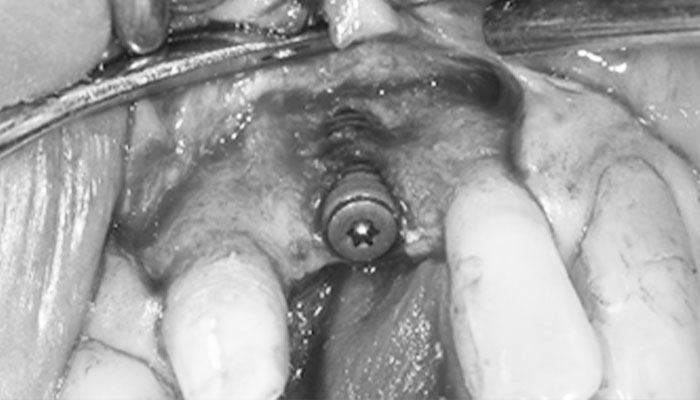

2.インプラント埋入

インプラントを埋入すると外側が露出しました。